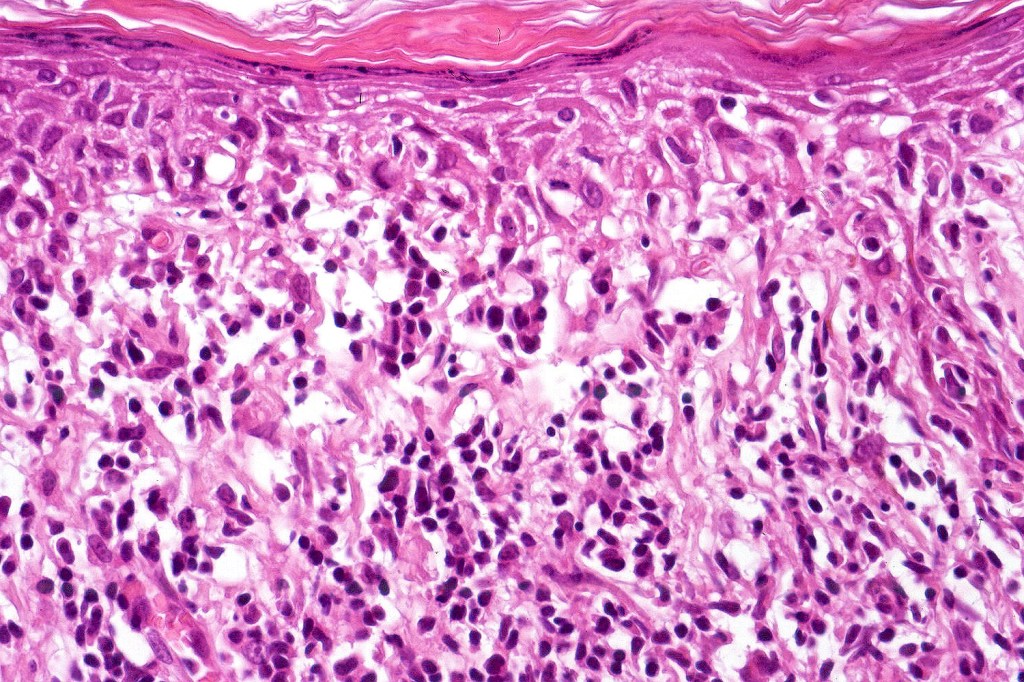

Histological features

The histological hallmark of mycosis fungoides is the presence of large atypical lymphocytes with a convoluted/cerebriform nuclear border (Sézary cells). These may be found at the epidermal-dermal jnuction and as collections within the epidermis (Pautrier microabscess). These are most easily found in plaque stage disease. The epidermal component can be subtle in patch stage disease and is often lost in tumor stage dsease. The classification into patch, plaque & tumor stage disease is less helpful histologically as the features merge from one to the other. It is all a matter of degree.

Tumor Stage Disease

•Epidermotropism is often minimal or absent

•Dense, broad diffuse or nodular, dermal infiltrate often extending into the subcutaneous fat

•Abundant Sézary cells. Frequently accompanied by very pleomorphic forms

•Mitoses often abundant, frequently abnormal

•CD30 expression correlates with transformation (cells X4 size of small lymphocytes comprising 25% or more of the infiltrate or the presence of a distinct large nodule)